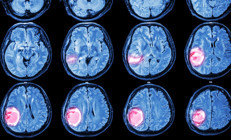

Adam, henüz 15 yaşındayken büyük bir beyin travması geçirdi ve birkaç gün komada kaldı. Bu, hayatını sonsuza kadar değiştirecekti.

Adam, acil yardım ekipleri gelince hemen hastaneye götürüldü ve yapılan bir dizi test sonucunda beyninde çok sayıda pıhtı olduğu ve kafatasının çatladığı tespit edildi. Ancak hiç kimse bu sorunların doğuştan mı yoksa yaptığı temas sporları nedeniyle mi oluştuğunu belirleyemedi.